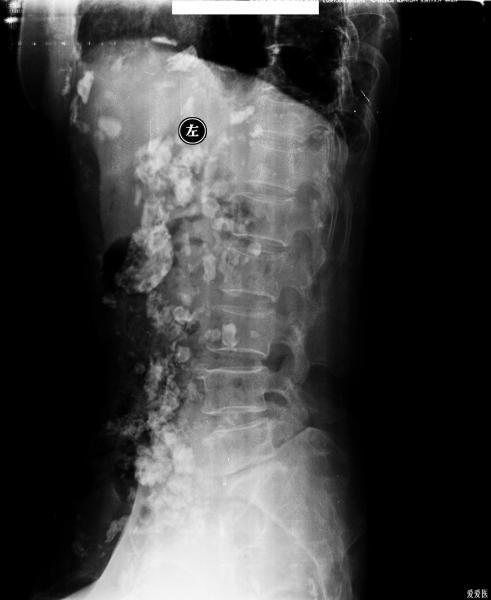

本帖最后由 274005 于 2011-3-18 15:14 编辑 患者是因为腰痛入院检查腰椎,检查前并没有服用过造影剂!

该患者摄腰椎正侧位后,发现腹腔非常罕见的广泛的钙化,而且双侧肋膈角变钝,左侧膈肌感觉明显向上有牵拉,左侧胸廓有塌陷。